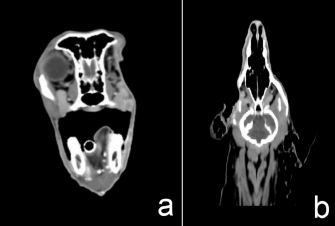

A female Cocker Spaniel dog aged 11 years was presented with a history of globe displacement of the right eye for 3 months. Ophthalmic examination revealed exophthalmos and third eyelid protrusion OD. Menace response, dazzle reflex, and pupillary light reflex were positive OU (oculus uterque; both eyes). Intraocular pressure (IOP) measured using a rebound tonometer (Icare®TonoVet; Icare Finland Oy; Helsinki, Finland) was slightly increased OD (IOP=29 mmHg) and within the normal limit OS (IOP=12 mmHg). Fundic examination was normal OU. Topical 1% brinzolamide (Azopt®; Alcon-Couvreur SA; Belgium) every 8 hours a day OD and artificial tears ointment with lanolin (Duratear: Alcon-Couvreur SA; Belgium) every 12 hours a day OU were prescribed. Computed tomography (CT; Optima CT600; GE Healthcare; USA) was planned to estimate the invasiveness of the lesion. CT demonstrated a mass effect with contrast enhancement in the right retrobulbar, maxilla, zygomatic, and temporal areas invading the right mandibular area with a periosteal reaction. Right zygomatic and temporal bone lysis was evident (Fig. 1). There was no detectable nodule metastasis in lung fields. The diagnosis was retrobulbar tumor OD. Cytologic examination at the retrobulbar area was sarcoma. Physical examination, hematology, and blood chemistry results were within normal limits. The planned treatment was tumor biopsy and surgical mass excision by exenteration combined with partial orbitectomy and zygomatic arch removal.

Fig. 1. Three-D (a), transverse (b), and dorsal (c) computed tomographic images in right retrobulbar, zygomatic, and temporal areas revealed a soft tissue mass involving periosteal bone with lysis of zygomatic and temporal bones.